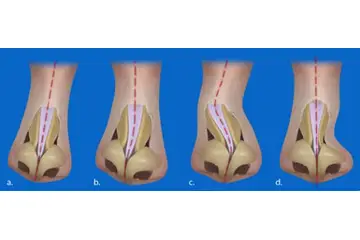

Diz Kıkırdak Hasarının Tanısı Diz kıkırdak hasarının tanısı, genellikle bir ortopedi uzmanı tarafından konulur. Tanı sürecinde şu yöntemler kullanılabilir:

Diz Kıkırdak Hasarının Tedavi Yöntemleri Diz kıkırdak hasarının tedavisi, hasarın ciddiyetine ve bireyin genel sağlık durumuna bağlı olarak değişir. Tedavi yöntemleri arasında şunlar bulunmaktadır: